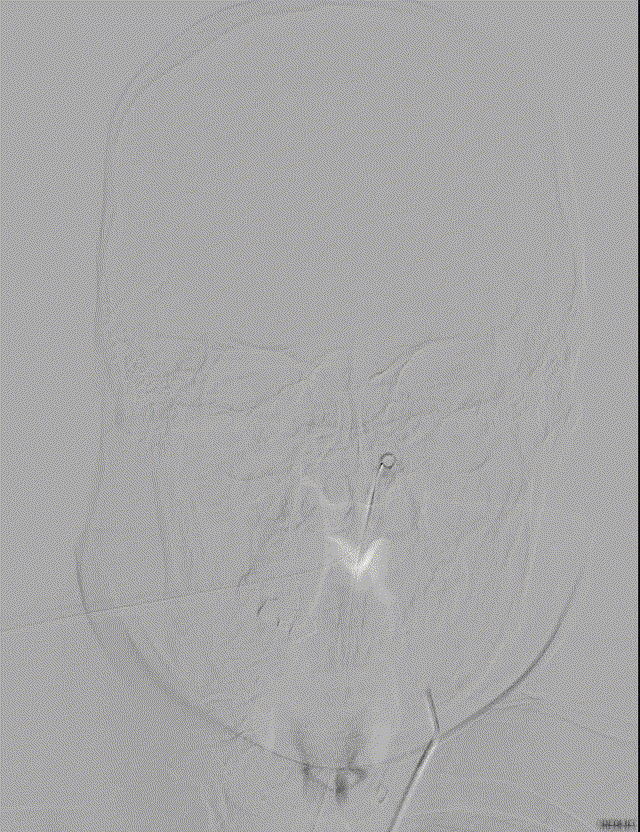

NeuroHawk Case 7